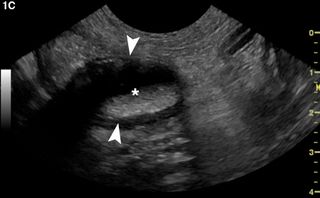

Examine the ultrasonograms, study the exam findings, and see if you can name the cause in this feline patient with hematuria and recurrent UTIs.